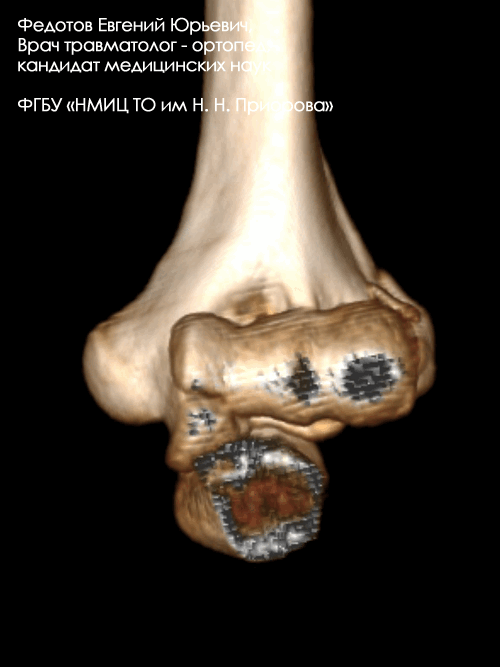

Закрытый внутрисуставной перелом головочки, блока мыщелка и наружного надмыщелка плечевой кости со смещением.

Операция: открытая репозиция отломков дистального мыщелка плечевой кости, наружного надмыщелка, остеосинтез пластиной и винтами.

Закрытый внутрисуставной перелом головочки и части блока плечевой кости со смещением.

Операция: открытая репозиция отломков головочки и части блока плечевой кости, остеосинтез винтами.